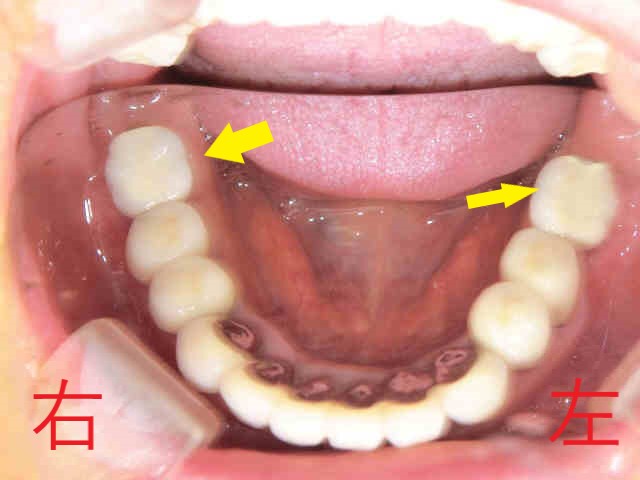

左上の写真は治療終了後の上顎を下から見たもので、右上は治療終了後の下顎を上から見たものです。今回の治療で咬合高径を高くした目的は、患者様の主訴である“上顎前歯の出っ歯”を解消するためだけではありません。低い咬合高径のままでは、インプラントに被せ(冠)を装着すること自体が難しかったからです。

なお、下顎の写真で黄色矢印の歯がインプラントの被せ(冠)です。埋入したインプラントは2本ですが、長期にわたって良好な口腔環境を維持するために非常に重要な2本となります。

もし患者様がインプラントをご希望されなかった場合、左右とも部分入れ歯を装着していただくことになったでしょう。入れ歯は、天然歯やインプラントによる人工歯と比べて咀嚼能力が低くなるという報告があります。また、入れ歯を支えるために前方の歯にバネ(クラスプ)がかかるため、ご自身の歯に大きな負担をかけてしまった可能性があります。結果として、インプラントを選択された場合と比べて長期予後が悪くなる可能性が高かったと考えられます。